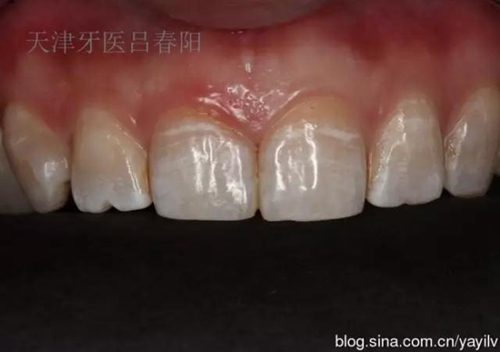

前牙齲洞的美學(xué)樹脂充填修復(fù) 科貿(mào)嘉友收錄

發(fā)一個最近完成的病例吧,雖然齲洞不大,但是挺好玩的,我自己認為。